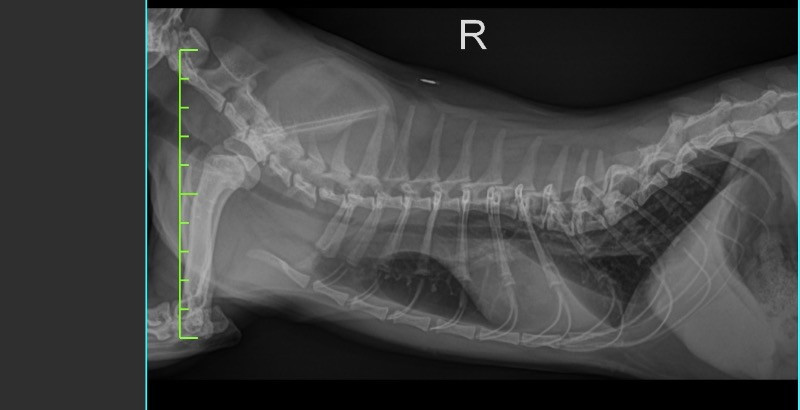

Anni安妮???????? 2026-02-13 貓咪10月大想詢問還有沒有機會不要透過開刀之外的方式矯正背部脊椎凹陷的問題 目前是透過骨科專科穿矯正馬甲將下腹骨骼拉開讓胸腔部分擴大 減少肺及心臟壓迫 0 分享–– 我也要提問